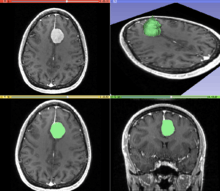

Segmentation

Segmentation is the process of partitioning an image into different segments. In medical imaging, these segments often correspond to different tissue classes, organs, pathologies, or other biologically relevant structures.[1] Medical image segmentation is made difficult by low contrast, noise, and other imaging ambiguities. Although there are many computer vision techniques for image segmentation, some have been adapted specifically for medical image computing. Below is a sampling of techniques within this field; the implementation relies on the expertise that clinicians can provide.

- Interactive Segmentation: Interactive methods are useful when clinicians can provide some information, such as a seed region or rough outline of the region to segment. An algorithm can then iteratively refine such a segmentation, with or without guidance from the clinician. Manual segmentation, using tools such as a paint brush to explicitly define the tissue class of each pixel, remains the gold standard for many imaging applications. Recently, principles from feedback control theory have been incorporated into segmentation, which give the user much greater flexibility and allow for the automatic correction of errors.[7]